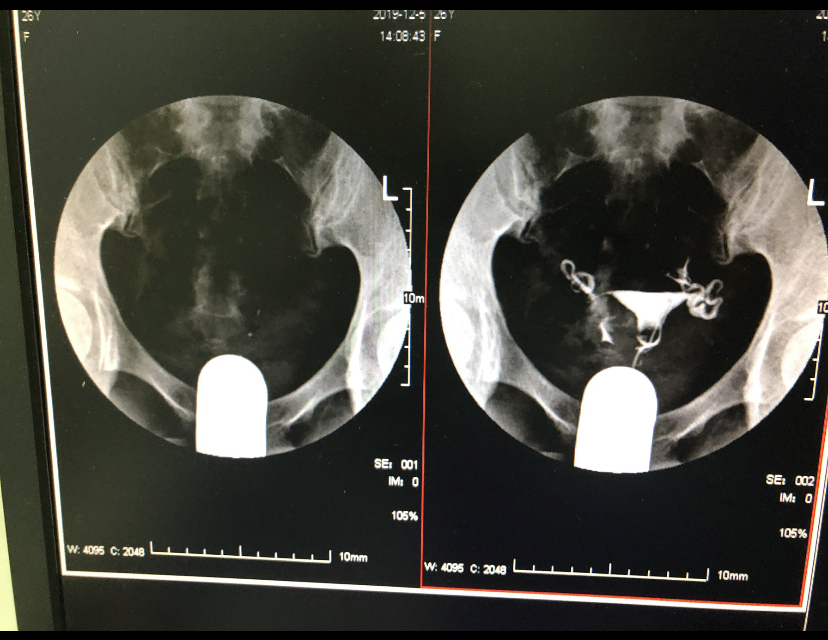

做完输卵管造影第六天了小腹还是感觉沉甸甸的如

可以热敷腹部,如果有发热,腹痛加剧,白带量多,有异味,随时就医